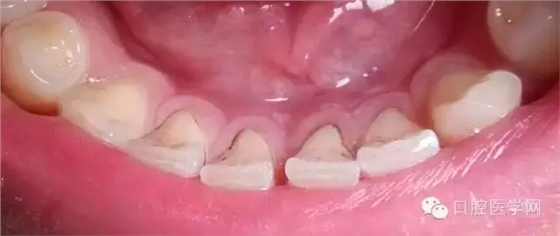

另一種則是牙齒出現(xiàn)了或深或淺的齲壞,從外面看就表現(xiàn)為一個黑點,通常位于窩溝點隙(牙面上點狀或線狀凹陷)。齲齒的罪魁禍?zhǔn)资强谇恢械哪承┘?xì)菌,但它們破壞牙齒也是需要時間的,從初期的變色到最終形成齲洞,通常需要1年半到兩年。在此期間,我們多留心自己的牙齒,完全可能把齲壞扼殺在萌芽階段。如何才能及時發(fā)現(xiàn)這種隱匿的蛀牙呢?找位好牙醫(yī),半年檢查牙齒!

一旦確認(rèn)牙齒上的小黑點是齲齒就應(yīng)該盡早修補,以阻止病變的發(fā)展。如果任由其繼續(xù)發(fā)展就會變成明顯的齲洞,這時患者會對冷熱酸甜等食物刺激敏感;當(dāng)損傷進一步到達牙髓(即老百姓說的“牙神經(jīng)”),就會疼痛難忍,嚴(yán)重影響日常生活。臨床上見到很多人都會等到牙痛得受不了,才到醫(yī)院就診。這時通常不能靠單純補牙來解決問題,可能還要做根管治療甚至拔除患牙、進行假牙修復(fù),費時費力又費錢,人還遭罪,可謂“小洞不補,大洞吃苦”。